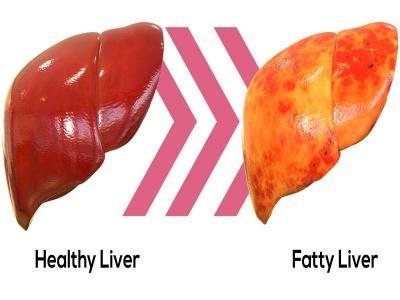

लिवर शरीर का सबसे महत्वपूर्ण अंग है। अगर आंवला का नियमित रूप से सेवन किया जाए तो यह लिवर को मजबूत करता है। इससे उसकी कार्यप्रणाली सही रहती है। आंवला टॉक्सिक एलिमेंट्स को शरीर से बाहर निकालने का काम भी करता है। ज्यादा शराब पीने से लिवर पर पड़ने वाले बुरे असर को भी आंवला कम करता है।